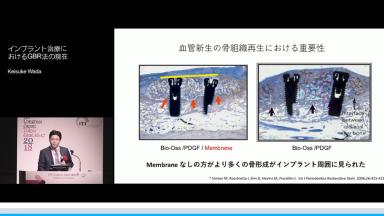

従来のGBRにおいては細胞供給、血管新生、移植材、成長因子が重要であった。一方で、マテリアルやテクニックの革新によって、より予知性の高いGBRが可能となった。Bone Ring Techniqueなど新しい骨増生法についても紹介する。